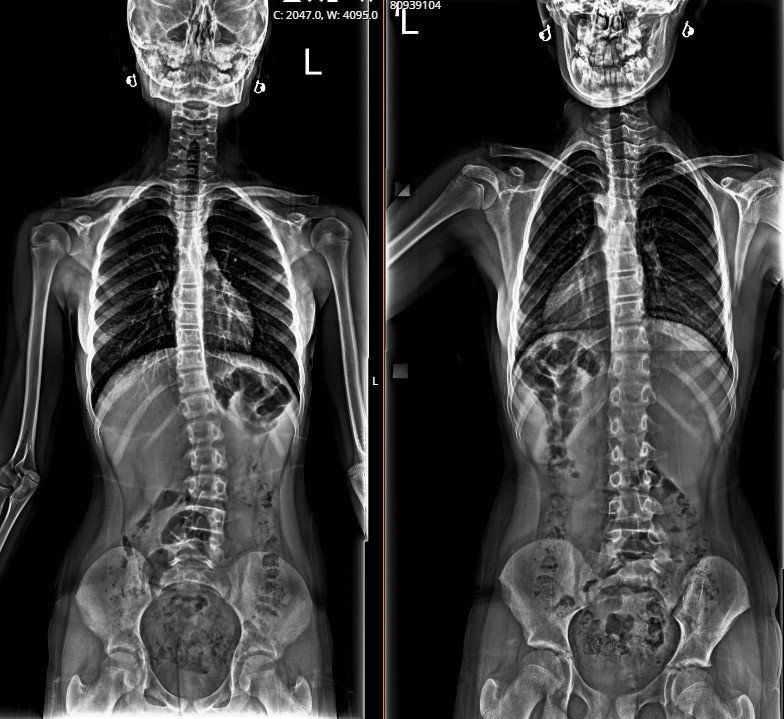

"Melis, bir buçuk yıldır dış hekim tarafından skolyoz takipli, bize kontrole geldi. Değerlendirdiğimiz zaman; 26 derece skolyoz olduğunu tespit ettik, nedenini araştırırken pelvik dengesizlik dediğimiz leğen kemiğinde bir dengesizlik olduğunu değerlendirdik. Yaptığımız klinik değerlendirmeler ve fizik muayene sonucu; bacakta eşitsizliğin dengelendiği zaman, skolyozun fayda görebileceğini öngördük. Yaklaşık 1,5 cm yükseklik ayağına uygulayarak tekrar röntgenini çektiğimizde, skolyoz derecesinin sıfıra yakın bir dereceye indiğini gördük. Sonrasında Melis'e tabanlık verdik, herhangi bir korse ya da cerrahi tedavi olmadan derecesini bu şekilde takip etmeyi düşünüyoruz. Takiplerimizde düzenli aralıklarla yaptığımız değerlendirmelerde ve röntgen kontrollerinde herhangi bir ilerleme olmazsa, süreci bu şekilde tamamlamayı planlıyoruz. Herhangi bir ilerleme veya ekstra bir ihtiyacı olduğunda da yakın takiplerle, gerekirse korse gerekirse fizik tedavi gerekirse de cerrahi olarak müdahale edebiliriz."

Melis Baş'ın aile öyküsünde de omurga eğriliği olduğunu aktaran Bozduman, taban yükseltme konusunun belli kriterleri olduğuna dikkati çekerek bu yöntemin herkese uygulanabilecek bir yöntemi olmadığının altını çizdi. Bozduman, "Taban yükseltme konusunu uygularken belli kriterlerimiz var, her çocukta herkeste uygulanabilecek bir uygulama değil. Bunun için kalça eklemlerinde ya da diğer başka hastalıklarda değerlendirme yaparak, bir hekim gözüyle bunu uyguluyoruz. Her hasta için "Tabanı yükselttim, omurgayı düzelttim" gibi bir yaklaşım doğru değil. Yeterli deneyime sahip ortopedi ve travmatoloji uzmanları tarafından yapılması ve tedavi edilmesi gereken bir yöntem, bu konuda deneyimi olmayan kişilerde ekstra farklı problemlerin ortaya çıkabilme riski var. Genel anlamda biz çocuğun ayağının altına bir buçuk santimlik defter kitap koyup, yükseltip, röntgen çektiğimiz zaman güzel ve hoş görünüyor ancak deneyimsiz ellerde bu başka problemlere yol açacak bir durum. O yüzden bu konuda belli bir deneyim gerekiyor" dedi.